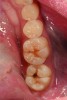

A 48-year-old patient presented with an old, failing Class I alloy restoration and showed recurrent decay on the lower molars (Figure 9). After the existing alloy was removed, the remaining tooth structure was evaluated. It was determined that despite the significant extent of caries present, it would be possible to perform a minimally invasive procedure using an injectable composite resin and an RMGI (Figure 10).

After removing the infected dentinal layer, a caries-detection stain was used to determine if further tooth removal would be necessary. On removal of all infected dentin, a chlorhexidine gluconate swab (CAVITY CLEANSER™ 2% Chlorhexidine Digluconate, BISCO, Inc.) was used to remove any surface bacteria on the prepared site. Next, a polyacrylic acid scrub was performed for 20 seconds to condition the dentin surface. An RMGI (GC Fuji II LC) was sculpted and light-cured to cover the affected and unaffected dentin.4,13,18,19 After the RMGI liner was fully cured, a micropreparation diamond bur (830RM.FG.009, Komet USA) was used to refine the internal form of the preparation. Marginal beveling to a 45° taper was completed along the cavosurface of the final tooth preparations.15

A dentinal adhesive resin was used to further seal the cavity preparation. Using a seventh-generation adhesive (ALL-BOND UNIVERSAL), a polymer chain union was created between the composite resin and RMGI.16 Following proper placement of the adhesive resin, an injectable composite resin (G-ænial Universal Flo) was placed over the RMGI, causing intimate union between the materials. An incremental build-up technique using the injectable composite resin was then easily employed to anatomically reconstruct the tooth.21-23 Because the selected resin has an excellent depth of color, a natural-looking result was achieved with a single shade of resin.24,25

CASE 2 RESTORATIVE TREATMENT (9.) Failing Class I alloy restoration and fissure decay on lower molars. (10.) Modern minimally invasive dentistry preparations on both molars. Notice the moderate decay lesion under the failing alloy. (11.) After placement of resin-modified glass ionomer liner, an injectable composite resin is the ideal material for these conservative restorations.